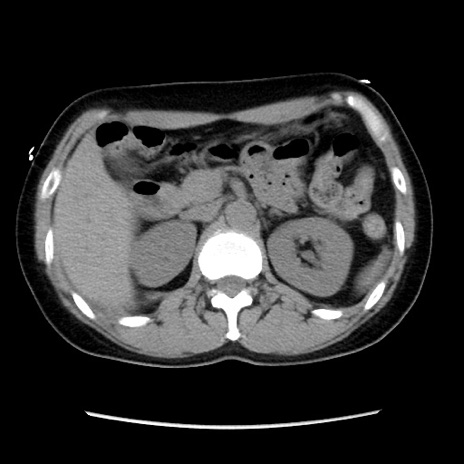

症例10(横断像)

【症例】 50歳代女性

【主訴】 腹痛

【現病歴】前日生レバーを食べた。今朝に排便あり。 昼前に突然発症の腹痛を生じ、当院救急外来を受診した。

【既往歴】 子宮筋腫にてで子宮全摘後

【身体所見】 意識清明、腹部:平坦、軟、下腹部やや左を中心に圧痛・反跳痛あり、筋性防御あり

【データ】WBC 7800、CRP 0.07